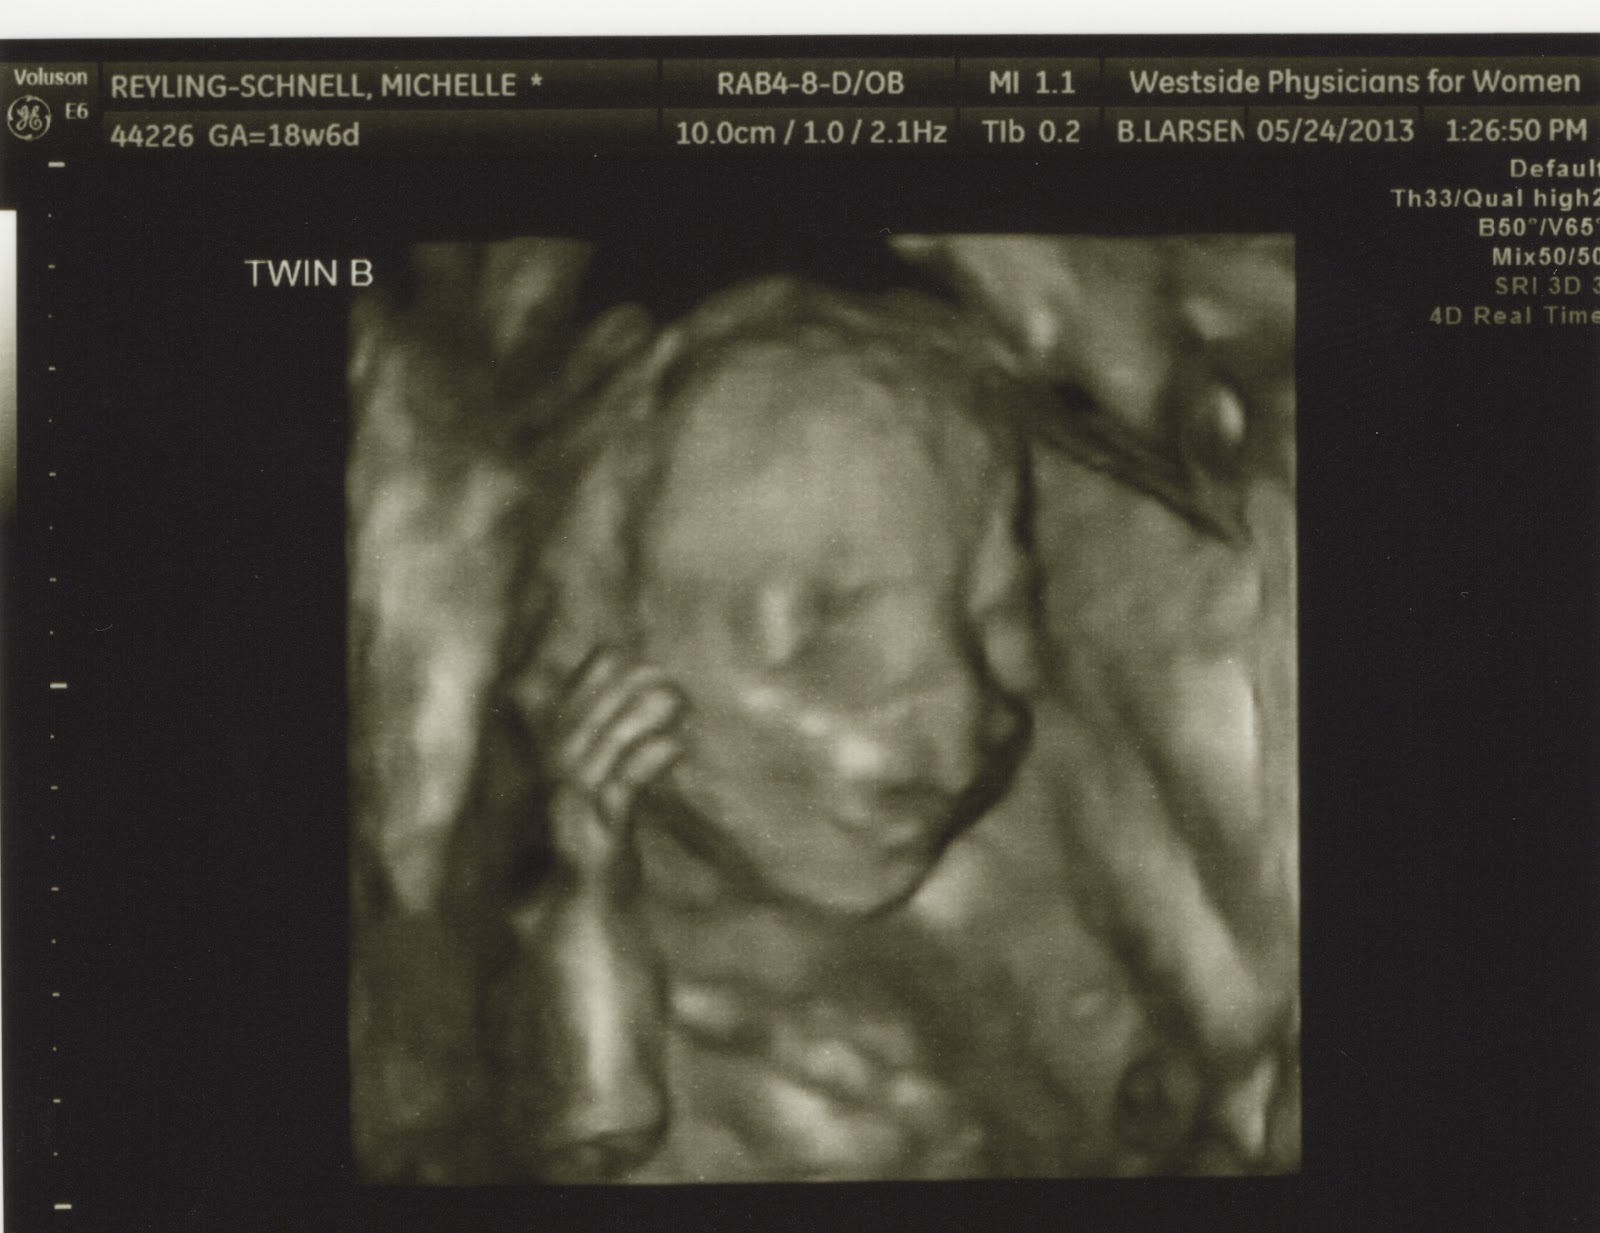

Schnell Baby B

We had our 19 week anatomy scan today. We found out the genders but you will all have to wait for another week! Both babies were measuring nearly the same and both were right on track!